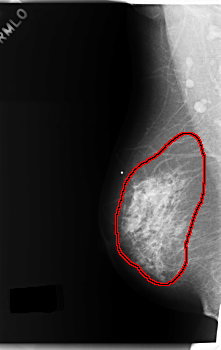

C_0179_1.RIGHT_MLO

RIGHT_MLO LINES 5944 PIXELS_PER_LINE 3744 BITS_PER_PIXEL 12 RESOLUTION 50 OVERLAY

FILE: C_0179_1.RIGHT_MLO.OVERLAY

TOTAL_ABNORMALITIES 1

ABNORMALITY 1

LESION_TYPE CALCIFICATION TYPE PLEOMORPHIC DISTRIBUTION REGIONAL

LESION_TYPE MASS SHAPE IRREGULAR MARGINS ILL_DEFINED

ASSESSMENT 5

SUBTLETY 5

PATHOLOGY MALIGNANT

TOTAL_OUTLINES 1

BOUNDARY